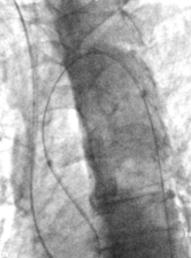

Routine access site selection- femoral

![]() |